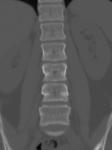

脊椎CT検査

椎体の変形や骨折、配列の乱れ、腫瘍などを任意の断面で観察することができます。

画像処理によって、立体的に表示させることも可能です。